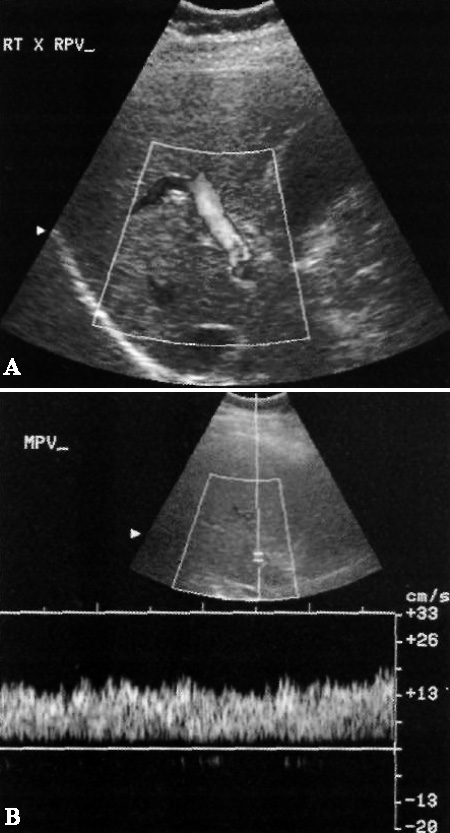

После установки шунта кровоток в правой и левой ветвях воротной вены должен быть гепатофугальным, что свидетельствует об отведении портального кровотока от печени в шунт. Поток в стволе воротной вены должен оставаться гепатопедальным (фото 12).

Фото 12. Портальный кровоток у пациента с TIPS. На цветовой допплерограмме в воротной вене определяется гепатофугальный венозный кровоток